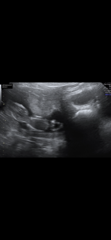

And these are my window to the womb ones from 2 days earlier at 12+4

Private Scan- Clinic Recommendations